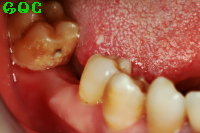

▼インプラント後![]() |

下あごの右奥歯にインプラントを植立するという手術でしたが、痛みはとくに感じませんでした。ほとんど意識がありませんから、起きたらもう終わっていたという感じです。

インプラントにして非常に満足しています。ほとんど自然の歯と変わらない仕上がりと噛み心地にとても満足しています。